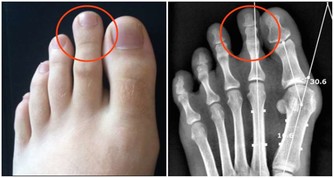

這是因為感冒時亂吃抗生素就會讓腎臟受損,可是如果拖著不去治療,看似不太嚴重的感冒、咽喉炎都會引發腎臟疾病。除了常見的呼吸道感染外,其他肺炎、肝炎等感染性疾病也會引發不同類型的腎病。